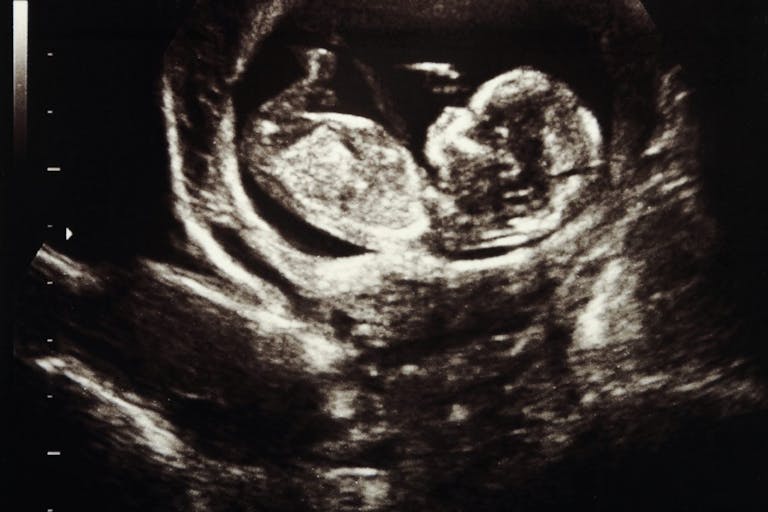

In fact, 65 of the 68 Planned Parenthood locations contacted told the women that they only provided ultrasounds on abortion patients. The facilities even had a policy that ultrasounds were only used to date the pregnancy before abortion procedures. They had no interest in helping pregnant women who wanted to have their babies. The investigation revealed that except in very rare cases, Planned Parenthood only does ultrasounds after the woman has agreed to have an abortion.

If Planned Parenthood is really about choice they would show women the ultrasound. And they don’t. […] When we got our new little 4D, state-of-the-art ultrasound machine in Storm Lake, the GE guy pulls up in his truck to deliver it. […] He’s got this fancy little machine that probably cost, I don’t know, $100,000 probably. […] He rolls it in, and he’s all excited about it because it’s really state-of-the-art, hot off the factory, and he wants to show me how it works. So I go back and he’s showing me all these bells and whistles and all these things on this little machine, and he gets to the button that says ‘print’. And he looked up at me for the first time and he said, ‘I guess for what you’re using this machine for, you’ll never print a picture.’ And I said, ‘No. Planned Parenthood will never print a picture.’ And of course, not only would they never print a picture, but they turn the monitor away so the mom can’t see it.

Planned Parenthood would never print a picture to give to the mother because this might dissuade her from going through with her abortion. Women were never allowed to see the babies that Planned Parenthood was about to kill.